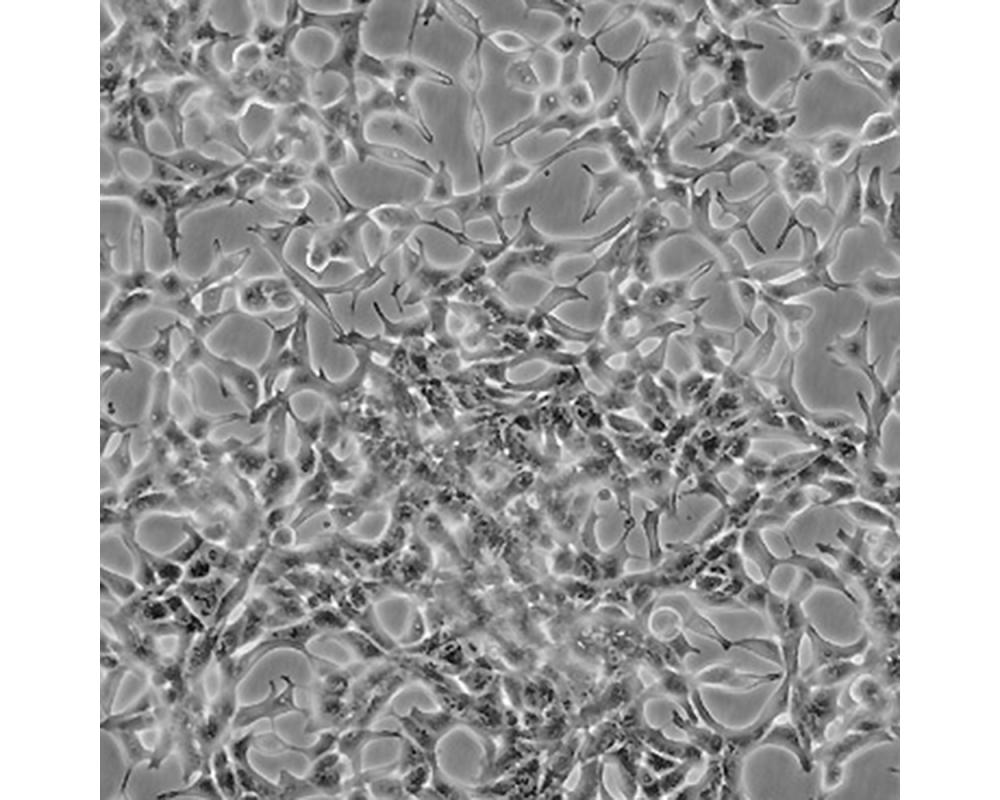

人前列腺癌細胞

前列腺癌;左鎖骨上淋巴結轉移;男性

形態特征

上皮細胞

生長特性

人前列腺癌細胞LNCaP克隆FGC是從一位50歲白人男性(血型B+)的左鎖骨淋巴結針刺活檢中分離,該患者經確診為前列腺癌轉移。 這株細胞對5-α-二氫睪酮(生長調節子和酸性磷酸脂酶產物)有響應。 這株細胞并不形成一致的單層,而是形成集落,在傳代時可以用滴管反復吹吸打碎。 它們僅僅輕輕地吸附在基底上,不形成匯合,很快使培養基變酸。 生長很慢。 傳代后48小時內不應擾動。 當培養瓶封包后,多數細胞從培養瓶底分離,懸浮在培養基中。 收到后,在通常培養單層細胞的條件下培養24到48小時,以合細胞再貼壁。